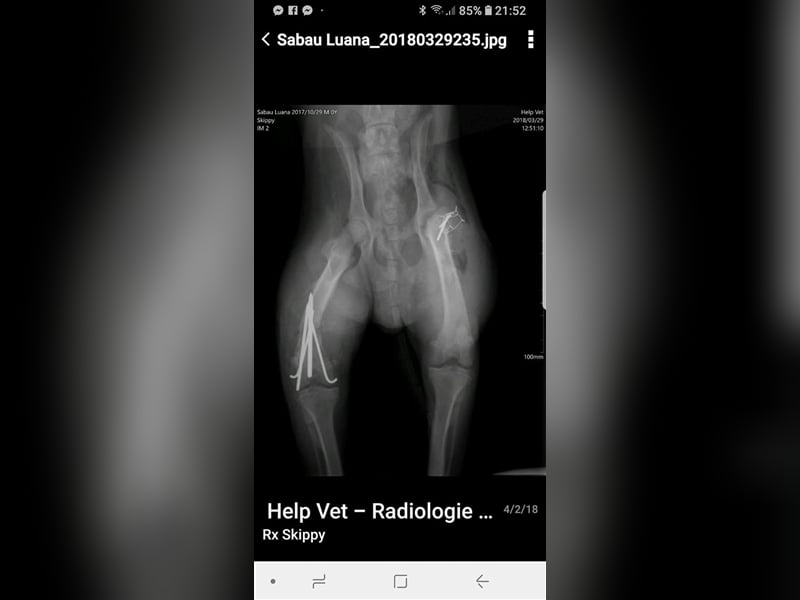

Skipper wurde im Oktober 2017 geboren, hat eine Schulterhöhe von knapp 50 cm und ist kastriert. Der Rüde wurde verletzt im Straßengraben gefunden, beide Hinterbeine waren gebrochen, doch er konnte erfolgreich operiert werden. Er ist inzwischen wieder flott auf seinen vier Beinen unterwegs, auch wenn sein Bewegungsablauf nicht ganz rund ist, so schränkt ihn seine minimale Behinderung nicht ein, fällt auch kaum auf und er ist auf seinen vier Beinen flott unterwegs. Der hübsche Rüde wird vielleicht nicht der ideale Begleiter für längere Joggingrunden oder Radtouren sein, aber nicht jeder Mensch ist ein Sportfreak und Skipper ist auf keinen Fall ein Couchpotato. Skipper lebt seit Juli bei einer Pflegefamilie in Dortmund zusammen mit anderen Hunden und kann dort gerne kennengelernt werden.